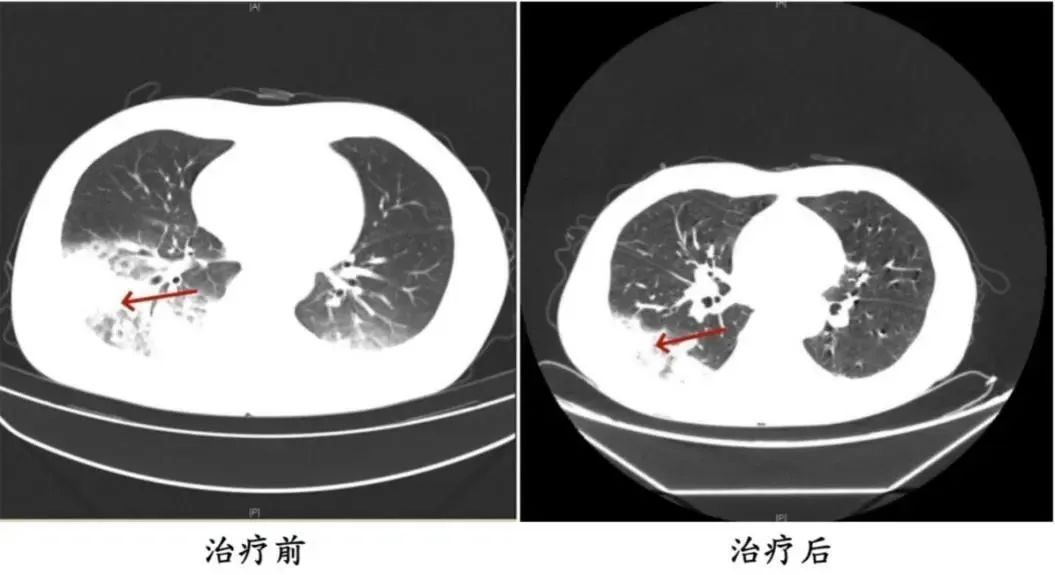

周先生治疗前后的肺部CT影像

医生询问发现,周先生此前驾车出差,因为天气热,他启动了久未清洗的车载空调,每天在车上的时间超过十个小时,回来后就出现了如上症状。经过检查,最终确诊为军团菌肺炎。